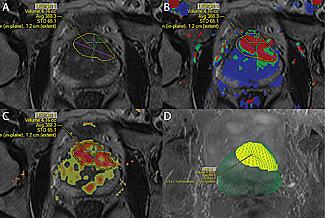

MRI technology was used to identify and locate a probable tumor (outlined in yellow) during a targeted prostate biopsy for a patient who had previously had multiple negative biopsies but had persistently high PSA levels. Resulting biospy confirmed presence of high-grade cancer.

For patients, the only added step to the prostate examination is the addition of MRI imaging, which occurs in a separate visit in advance of the biopsy exam. Working with David Karow, M.D., Ph.D., a UC San Diego Health System radiologist, Parsons uses sophisticated new tools and software – DynaCAD for Prostate with the UroNav fusion biopsy system – to combine the MRI with real-time, ultrasound-guided biopsy images in the clinic, resulting in what he calls a 3-D road map of the prostate.